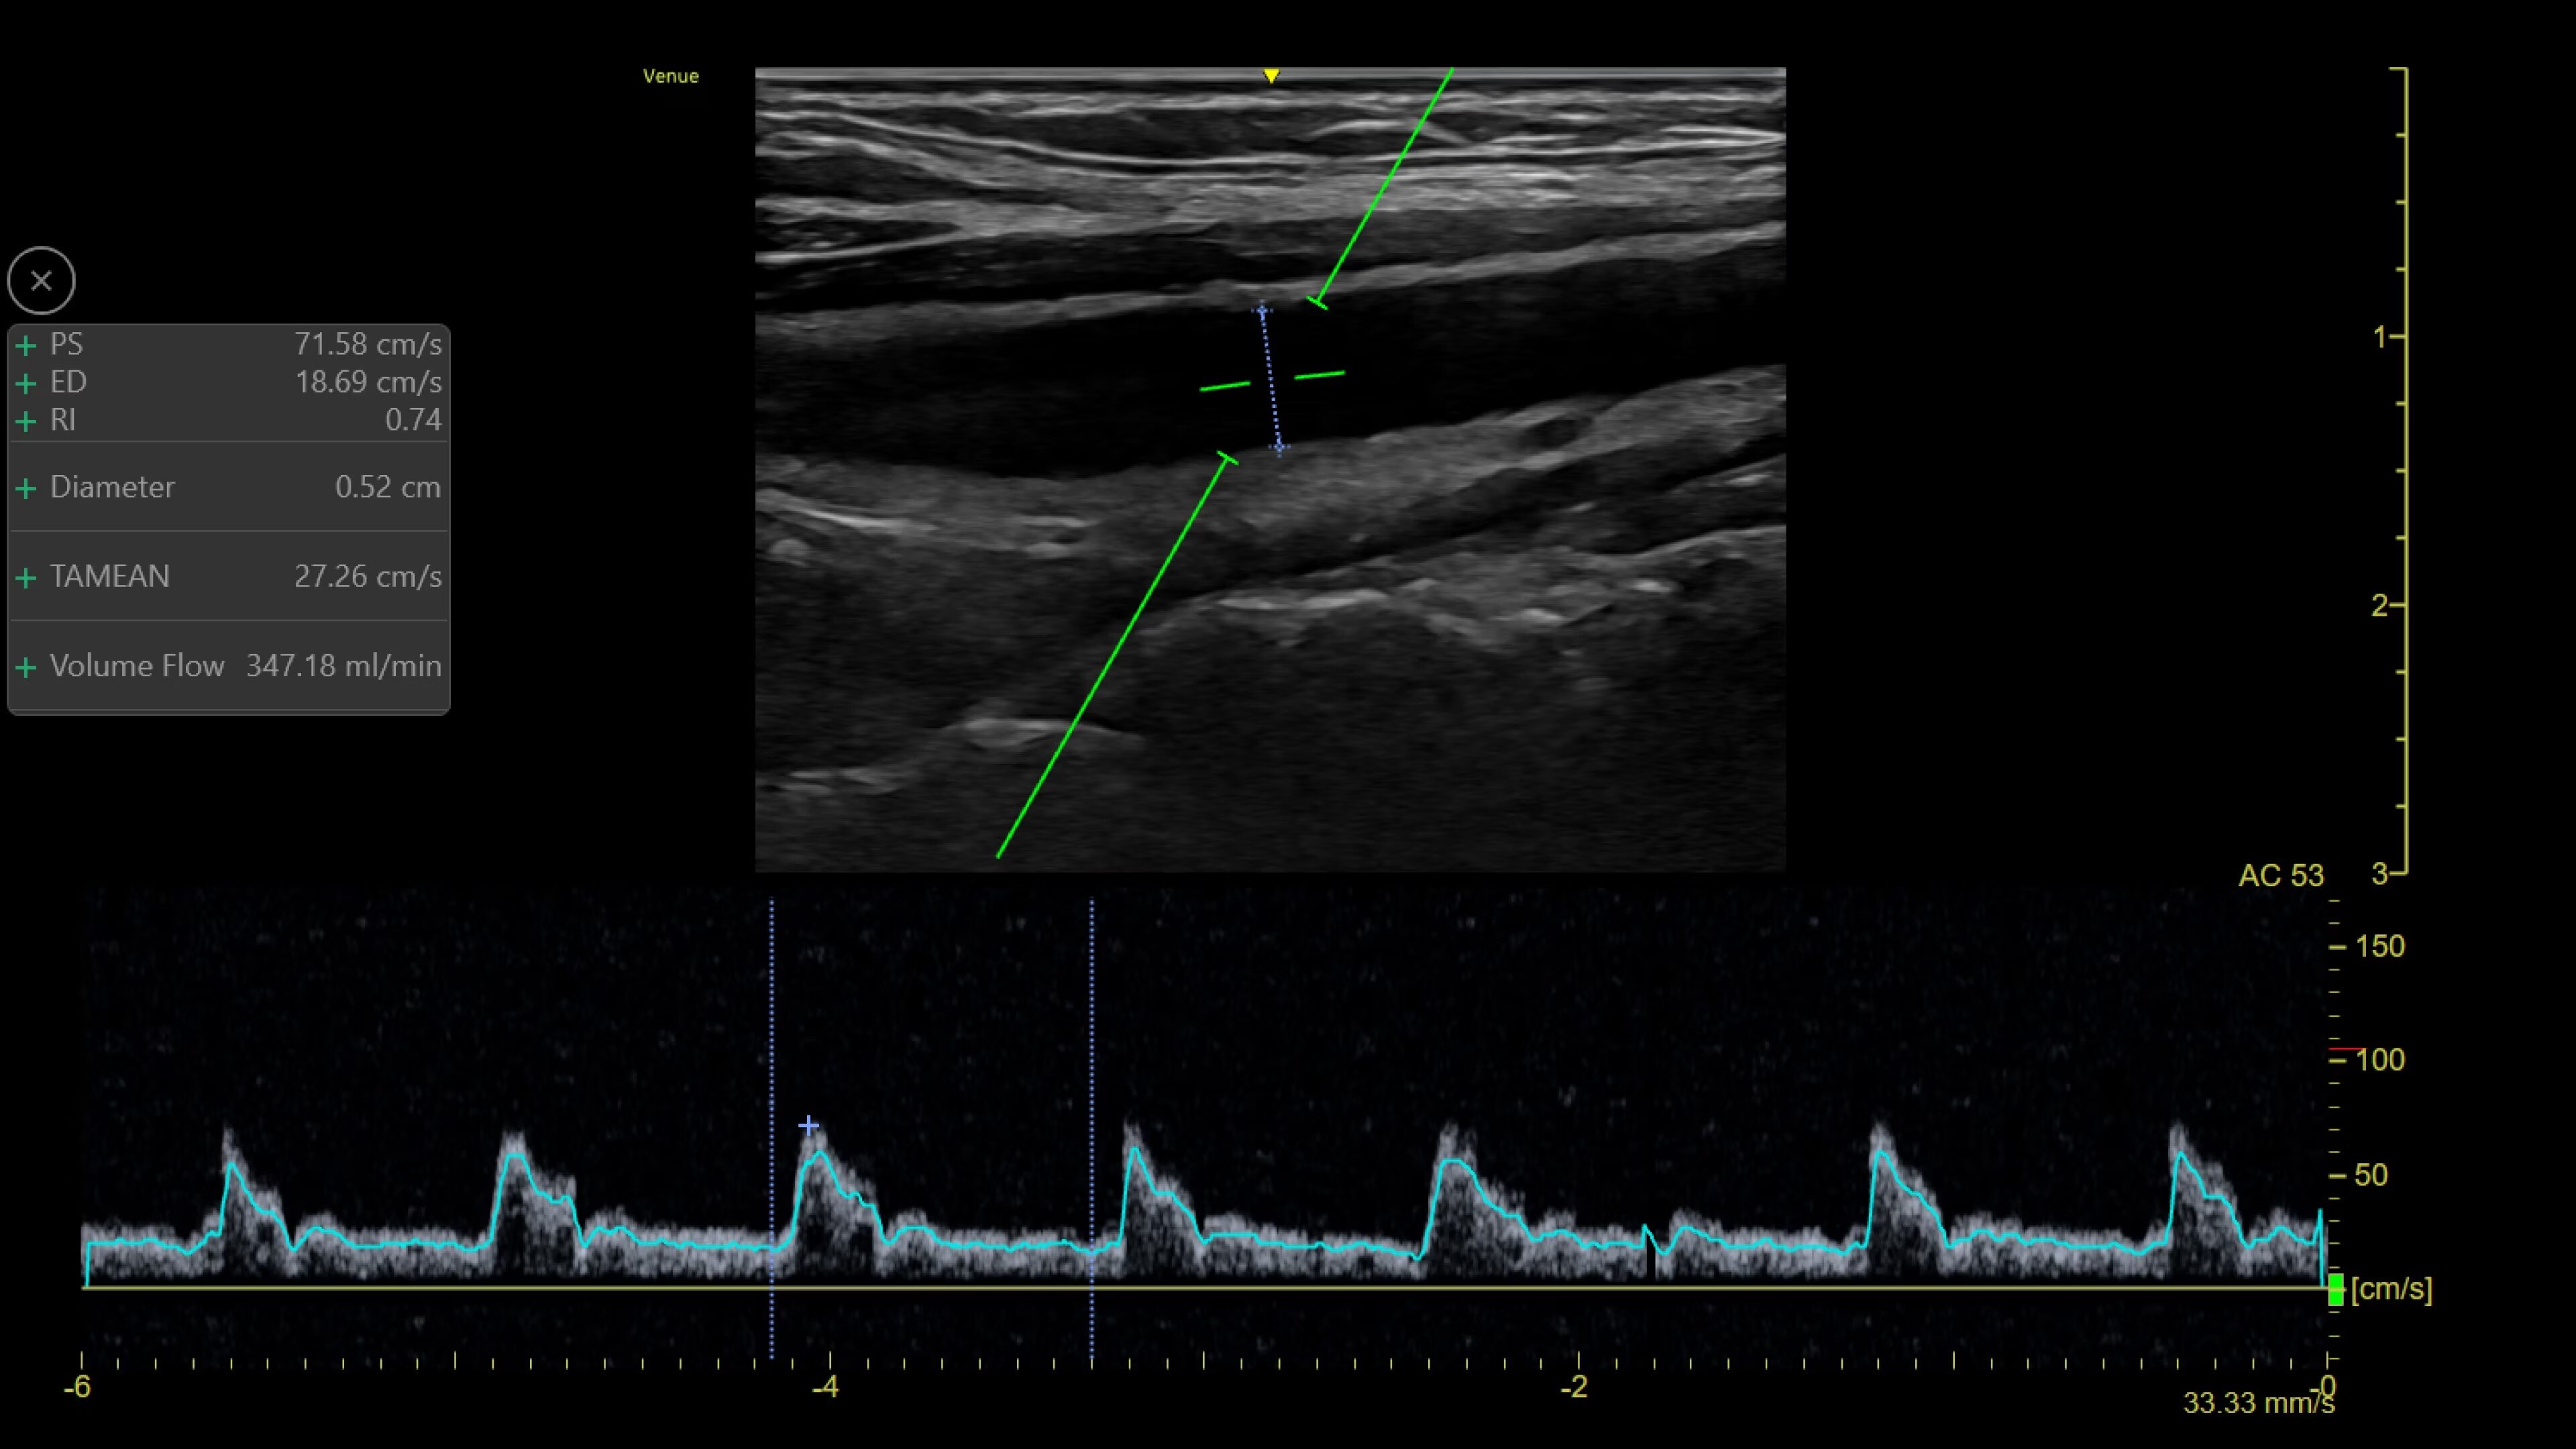

Catheter to Vessel Ratio

Accurate catheter selection tool

Selecting the wrong sized catheter can lead to catheter related thrombosis.2 Catheter to Vessel Ratio is a measurement tool that supports clinicians in selecting the appropriate sized catheter based on vessel diameter.